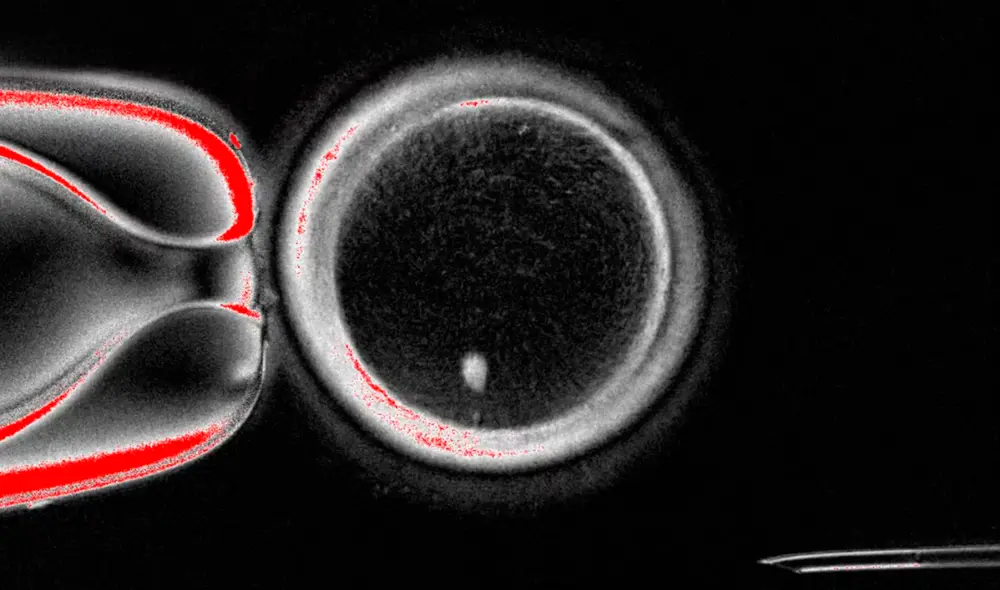

El equipo de Mitalipov utilizó en cambio la técnica que se utilizó para clonar a la oveja Dolly: los científicos extrajeron la mayor parte del ADN de un óvulo de donante sano y lo reemplazaron con la mayor parte del ADN de una célula de la piel de otra mujer.

A continuación, los investigadores básicamente manipularon el óvulo reconstituido para que se saltara las formas normales de división celular conocidas como mitosis y meiosis. En su lugar, los indujeron a pasar por un proceso diferente al que denominaron "mitomeiosis". Esto produjo 82 óvulos funcionales, informaron los investigadores.

Los investigadores luego fertilizaron los óvulos con espermatozoides para ver si podían convertirse en embriones. Y parece haber funcionado, al menos en un pequeño número de intentos, informan los investigadores. El 9% de los embriones resultantes se desarrollaron hasta la etapa de blastocisto, momento en el que se transferirían al útero de una mujer, informaron los investigadores.